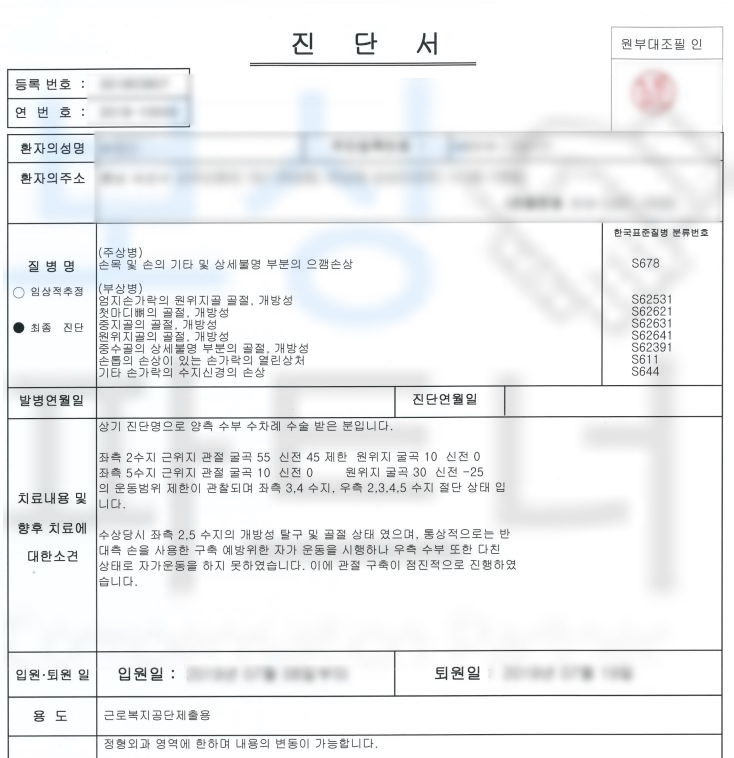

강@@님은 재해 당시 잔업 근무를 하던 날, 프레스 장비를 사용하던 중에 기계 오작동으로 인해 손가락이 으깨지는.. 사고를 당하셨습니다. 손가락의 상태는 심각했고 응급실 내원하여 수술을 받게 되었는데요, 수술을 실시하였음에도 손가락 으깸손상 s678 진단받아

강@@님은 손가락 일부가 절단될 수밖에 없었습니다. 산업 재해 근로자를 보호하기 위한 산재 보험을 통해 보상받을 수 있습니다.

**산재장해등급 5급 **인정받아

장해급여 연금으로 12,108,048원

지급받을 수 있었습니다. 산재장해등급은 다치고 수술했다고 해서 무조건 해당되는 것이 아닌 산재 장해판정 기준에 부합해야 지급되는 보험급여입니다. 강@@님의 상황을 보면 으깸손상 (압궤손상) s678 진단받아 무조건적으로 해당되어 보였지만

보상 파트너는 강@@님의 요양 기간 동안 의뢰인의 장해의 정도를 검토하고 미리 서류를 준비하였습니다. 요양 종결 시점 산재 장해급여 청구 시 종경 병원의 주치의와 함께 면담을 진행하여 객관적이면서 정확하게 장해판정이 이루어지도록 이끌었고 관할 공단의 장해판정까지 함께 주의 깊이 진행한 결과